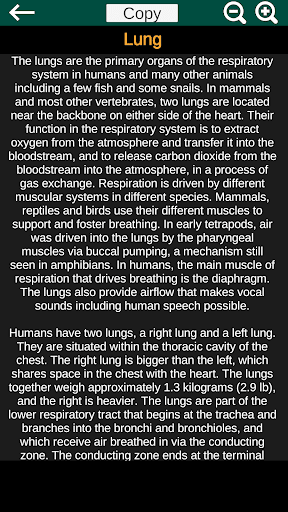

* Deskripsi masing-masing organ.